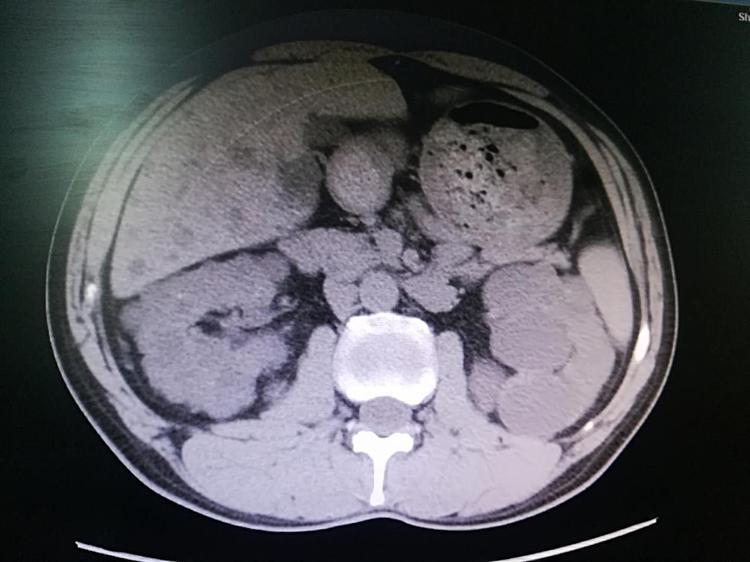

近期,我院泌尿外二科主任宋金喜團(tuán)隊(duì)成功進(jìn)行了1例復(fù)雜手術(shù):患者為中老年男性,主因“發(fā)現(xiàn)低鉀血癥近1年,全身乏2月余”入院,查腎上腺CT示:考慮右側(cè)腎上腺腺瘤,多囊腎,多囊肝。完善各項(xiàng)術(shù)前準(zhǔn)備后,在全麻下行“后腹腔鏡下右腎上腺腫瘤切除+右腎囊腫去頂減壓術(shù)”。術(shù)后患者恢復(fù)良好。(泌尿外二科)